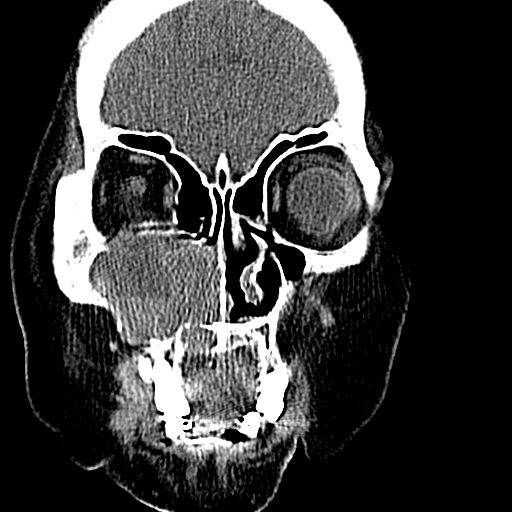

标题: CT19708:单侧上颌窦病变

老年患者,女。鼻塞多年。

考虑右侧上颌窦良性占位性病变,粘液囊肿可能性大;建议活检。

膨胀性生长,且骨质无破坏,说明时间久,良性;从密度,边缘看,内部还见坏死区,应该是实性肿瘤,定性,影像学无绝对的特异性

病灶密度很不均匀,骨壁膨胀中有断裂,考虑内翻乳头状瘤可能性大,粘液囊肿不排除

膨胀性生长,且骨质无破坏,说明时间久,良性;从密度,边缘看,内部还见坏死区,应该是实性肿瘤,定性,影像学无绝对的特异性,考虑内翻性乳头状瘤可能